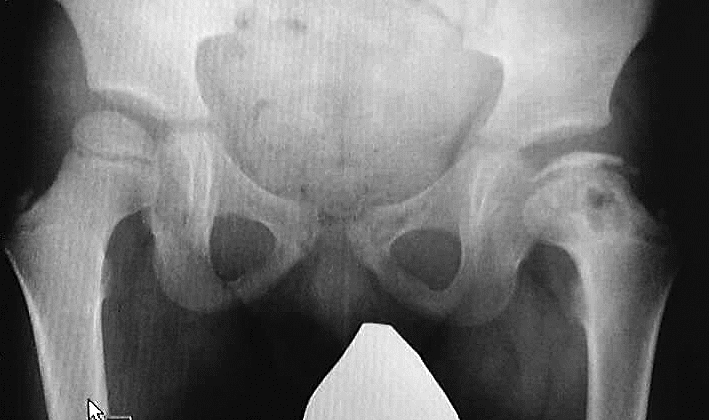

左図は手術前です。骨頭の外側の1部が臼蓋からはみだしています。右図のように骨切りをおこなって、骨頭の向きを変え、はみだした部分までも完全に臼蓋の奥深くに包み込みます。この手術は術前に骨の正確な計測を行い、手術ではその計画を厳密に実行します。皮膚切開の後には、筋肉の剥離、骨の展開、関節包の温存、金属の打ち込む方向、注意深い骨切り、下肢短縮を最小限に押さえる工夫、など、いずれをとっても慣れた術者が行わないと(少なくとも50例の経験は必要)重篤な合併症をおこすことがあります。

上図は10歳男子で、装具療法がうまくゆかないまま放置されていた例で、著しい変形があった例です。